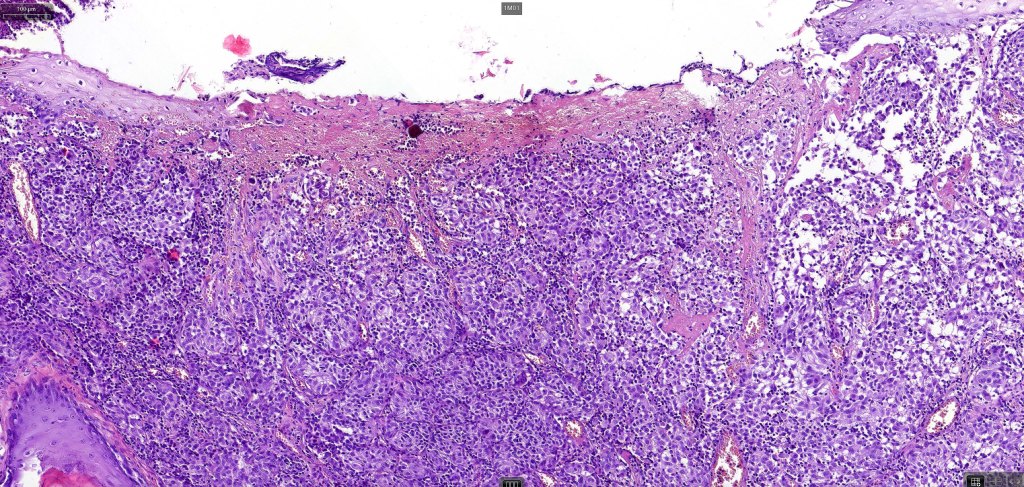

An exceedingly rare variant of melanoma. The term includes cases of melanoma that show features of an associated inherited bullous dermatosis such as epidermolysis bullosa or acquired immunobullous intraepidermal or sub epidermal bullous dermatosis such as pemphigus or bullous pemphigoid and cases where the blister develops directly overlying the melanoma in the absence of any underlying/associated blistering condition. It is generally recommended that measurement of the melanoma should be from taken below the blister/vesicle so as to avoid over-estimating tumor thickness.

Case courtesy of Dr. Antonina Kalmykova